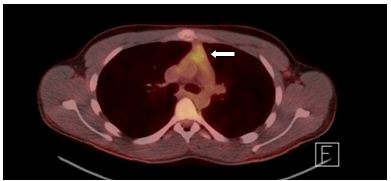

The patient was referred to thoracic surgery for a surgical biopsy as the diagnosis was in question. A left parasternal mediastinoscopy (Chamberlain approach) was performed. Pathology from this specimen revealed small fragments of thymic tissue with preservation of normal architecture. There was no histologic evidence to support malignancy and flow cytometry was negative for lymphoma. A positron emission tomography (PET) scan (Figure 4) revealed diffuse mild activity; the standardized uptake value (SUV) max was 3.9, consistent with benign thymic tissue. He was diagnosed with rebound thymic hyperplasia following the viral illness in the weeks prior to presentation.

Figure 4. Positron Emission Tomography (PET) scan of chest demonstrating soft tissue mass with mildly increased metabolic activity; standardized uptake value (SUV) max 3.9 (arrow).